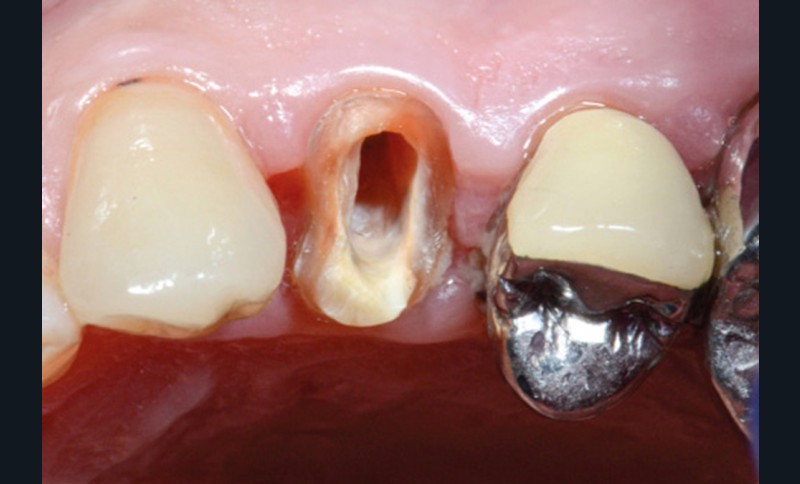

L’application stricte de ces règles élémentaires oriente donc préférentiellement, dans le cas de perte tissulaire modérée ou importante, vers la réalisation d’inlay-core (fig. 1a-b).